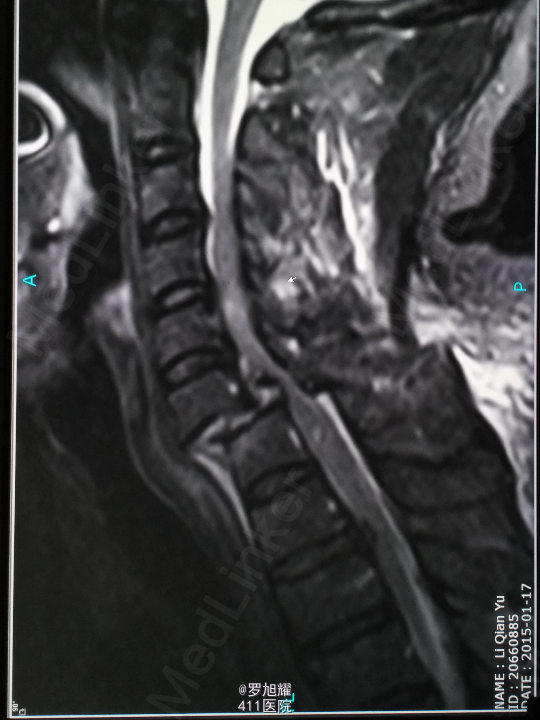

查体:双上肢前臂及以远感觉丧失,躯体自第二肋间平面以下感觉丧失。耸肩可,双侧三角肌、肱二三头肌肌力2级,腕关节屈伸、旋转及各指肌力0级。腱反射阴性,但球海绵体反射已经阳性。影像学检查示颈椎骨折脱位伴颈髓损伤。

诊断:颈6/7骨折脱位伴高位截瘫。处理:立即甲强龙冲击、脱水、保胃、营养神经治疗。首选治疗方案是颅骨牵引复位后前路融合固定,较后路稳定,出血也少,和家属谈话后开始颅骨牵引复位,4kg起步,每半小时增加1kg直至14kg,调整颈椎屈伸位,再加用手法牵引仍不能复位。改用备选方案,急诊行后路切开减压撬拨复位内固定,术后瘫痪症状部分改善。随访3月双上肢前臂及手部感觉恢复,仅双手掌尺侧及小指感觉障碍,双侧三角肌、肱二三头肌肌力4-5级,腕关节屈伸、旋转肌力左侧3级,右侧3-4级,但各指肌力仍0级。